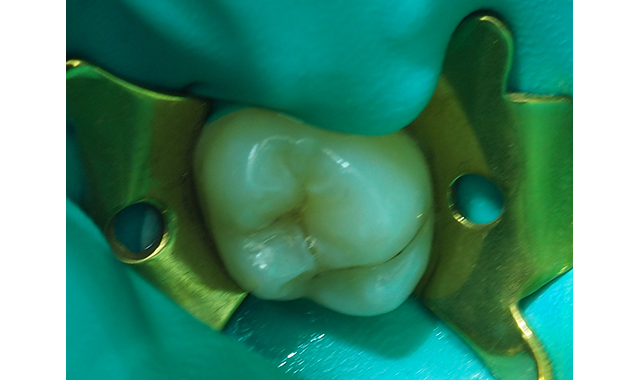

Fig. 2 Rubber dam placed post-anesthesia and the molar prepared with #330 carbide bur in high-speed handpiece with copious water spray.

After placement of the rubber dam, the preparation was performed with a high-speed handpiece using sufficient water spray and the carious dentin exposed (Fig. 2). The carious infected dentin was removed with a #4 round bur (keeping the dentin moist) in a slow-speed handpiece and with judicious use of a sharp spoon excavator (Fig. 3).

Fig. 3 The carious dentin has been carefully removed with a #4 round bur in a slow-speed handpiece and a sharp spoon excavator. The dentin is never dried and kept moist.